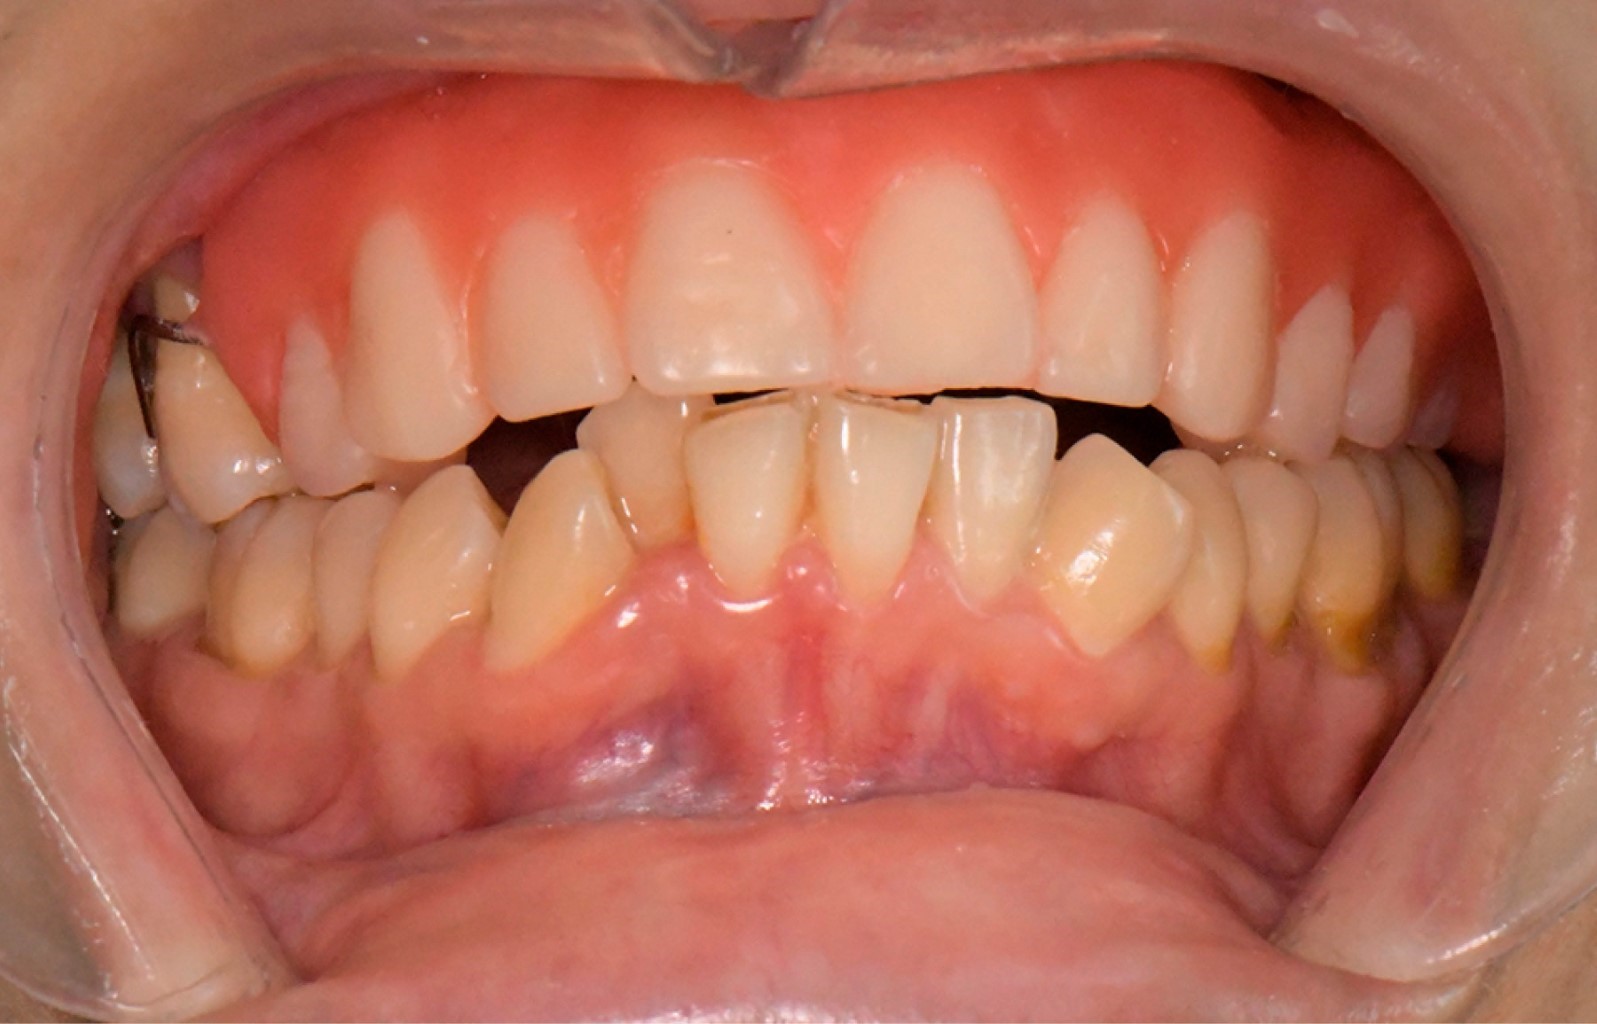

En 2025 fue referido al servicio de estomatología del INCan debido a movilidad grado 3 de piezas dentales del maxilar por pérdida de soporte óseo. Se discutió el caso con el servicio de radioterapia para autorizar extracciones dentales, y en conjunto con el servicio de cirugía maxilofacial se llevaron a cabo múltiples extracciones dentales y desbridamiento del secuestro óseo bajo anestesia local, sin complicaciones (Figura 3). Se indicó continuar con el tratamiento con PENTOCLO y el sujeto fue integrado a manejo paliativo integral, debido a la progresión sistémica de la enfermedad oncológica, con metástasis pulmonares y en otros sitios (Figura 4).

Figura 3

Figura 4